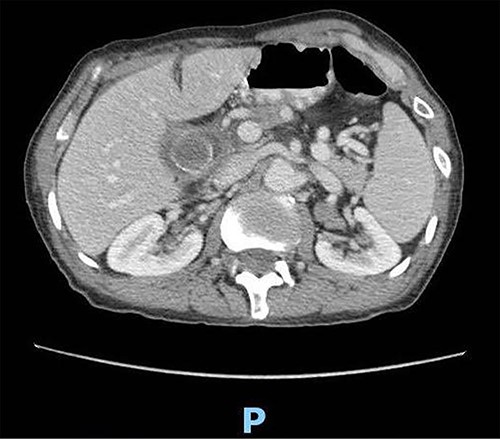

Upon clinical examination, the patient was vitally stable. Abdominal examination revealed a distended abdomen with generalized tenderness. Digital rectal examination revealed an empty rectum with no palpable masses. Laboratory investigations were unremarkable (Table 1). Abdominal X-ray was done (Fig. 2) and showed dilated large bowel loops suggestive of bowel obstruction. Enhanced CT scan of the abdomen and pelvis was obtained (Figs 3–5) and showed a dilated large bowel loop, with air fluid level. A 2.5-cm gallstone was noted, impacting the sigmoid colon and causing partial large bowel obstruction. There was evidence of pneumobilia with air foci within the gallbladder with a suspected fistula with the hepatic flexure.

Enhanced CT scan of the abdomen showing a gallbladder stone impacted at the sigmoid colon, with a significantly enlarged prostate causing narrowing of the rectosigmoid junction (sagittal view).